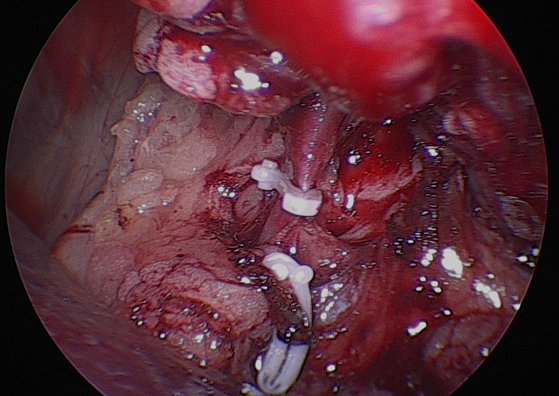

수술 과정은 다음과 같이 진행되었습니다.먼저종양이 위치한 신장을 후복막에서주변 조직과 분리하였습니다.

신장을 충분히 노출한 뒤, 신혈관을 순차적으로 처리했습니다.우선신정맥을 둔성으로박리하여 분리한 뒤, 클립으로 결찰하고절단하였습니다.

이어서 신동맥역시 같은 방법으로 둔성박리 후 클립 결찰후 절단하였습니다.

그 다음 신장에서 이어지는 요관을 따라 원위부로 추적하여 방광에 가까운 지점에서 둔성분리한 후 클립으로 결찰하고절단하였습니다.

이렇게 신장, 혈관, 요관이 모두 안전하게 분리된 것을 확인한 뒤, 적출된 신장을 수거 백에넣어 복강 내 오염 없이 외부로 제거하였습니다.

최소침습적 접근을 통해 조직 손상을 줄이고 통증을 최소화하면서, 종양을 안전하게 제거하는 데 중점을 두고 수술을 진행하였습니다.

환자는 고령이었기 때문에 수술 후 통증과 회복 부담을 최소화하고자 복강경을 이용한 최소침습적 신장적출술을시행하였습니다.수술 과정은 다음과 같이 진행되었습니다.먼저종양이 위치한 신장을 후복막에서주변 조직과 분리하였습니다.